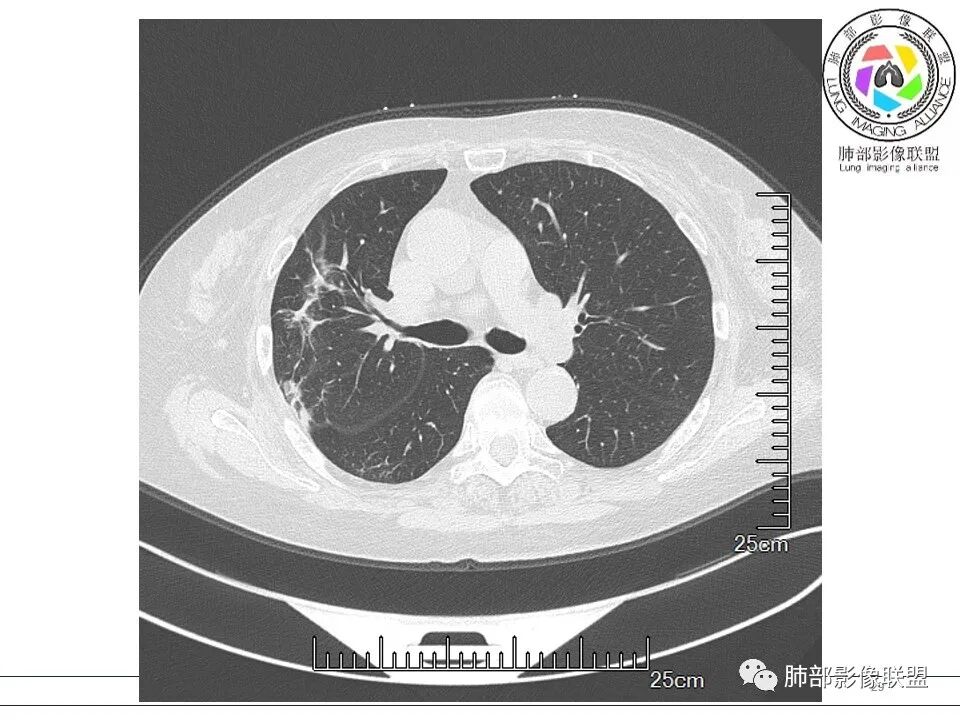

宇宙: 右肺上叶胸膜下结节,多结节融合,长轴平行胸膜,边缘模糊,周围长索条,胸膜牵拉,近端支气管充气扩张,考虑隐球菌,鉴别OP

衡妈: 老年女性,右肺上叶沿胸膜下不规则实性病灶,长轴平行于胸膜,有结节融合感,边缘部分彭隆部分平直,周围可见数条纤维灶影,病灶内可见充气支气管征未达远端,首诊考虑慢性炎性肉芽肿,隐球菌?机化性肺炎?建议增强扫描及ct下穿刺活检。

放射线 (王秀仙): 右肺上叶胸膜下结节样影,边缘平直收缩,胸膜牵拉,支气管进入病灶并扩张,部分支气管进入后阻塞,长轴平行于胸膜,周围可见片状及条索状影,隐球?机化性肺炎?

晨读:女,70,未诉症状。风湿性多肌痛病史,口服强的松等药物治疗。胸部CT:右肺上叶多发不规则斑片影,沿支气管分布,部分病灶侧向融合、平行于胸膜,边缘平直内收为主、部分彭隆,周围模糊晕、可见数条纤维灶影,胸膜牵拉,病灶内可见充气支气管征、管腔不畅,考虑慢性炎症,PC?OP?鉴别腺Ca、SCLC等。

良孑: 右肺胸膜下多发结节,长轴与胸膜平行,部分病灶有多结节融合,可见近端支气管充气征,有晕征及晕中软毛刺,长期口服激素病史,抗炎效果欠佳。病灶形态单一,无播散性树芽,结节内无支气管穿行,单侧发病,收缩力差,可排除TB,OP及淋巴瘤,综和考虑支持隐球菌

南边: 这个病例大方向没问题,炎性。目前大家都是考虑:隐球菌病、OP,其实这两个结论有重叠,而且这个病例很值得讨论,可惜,估计没有证实。影像特点:病灶长轴与胸膜平行,侧向融合特点明显,符合隐球菌病,问题是目前的状态,边缘收缩明显

内部支气管扩张,周围少量GGO,而且病灶离开了胸膜,附近长索条影,支持机化的改变

5、分布:隐球菌肺炎是肺泡性炎症,病灶分布多位于胸膜下,可紧贴胸膜,也可与胸膜邻近,病灶长轴与胸膜平行。(划重点,分布特点非常重要,因为隐球菌如果没有荚膜,会被巨噬细胞吞噬,在人体内是无法生存。隐球菌孢子吸入后,要有高浓度的CO2的条件下,才能形成荚膜,所以肺泡内、胸膜下多见)

8、晕征:病变早期可出现磨玻璃晕征,为周围炎性渗出或肺间质受累。

11、收缩力:可以较弱,也可以较明显伴有胸膜牵拉。